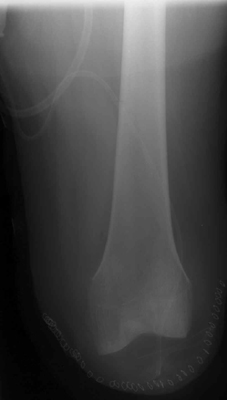

The knee disarticulation

results in an excellent weight-bearing stump. It is most often used in children and

young adults, but is nearly always avoided in the elderly and patient with ischemic

disease. Several advantages of the knee disarticulation include: 1) a

large end surface covered by skin and soft tissues that is naturally suited for weight

bearing; 2) a long lever arm controlled by strong muscles; 3)

increased stability of the patients prosthesis. A main disadvantage of the knee

disarticulation is cosmetic. The patient's prosthetic leg will have a knee that

extends far beyond his own knee in the sitting position. This tends to leave the

portion of the prosthesis below the knee dangling off the floor when the patient sits.

The image shown demonstrates an immediate post-operative knee disarticulation.